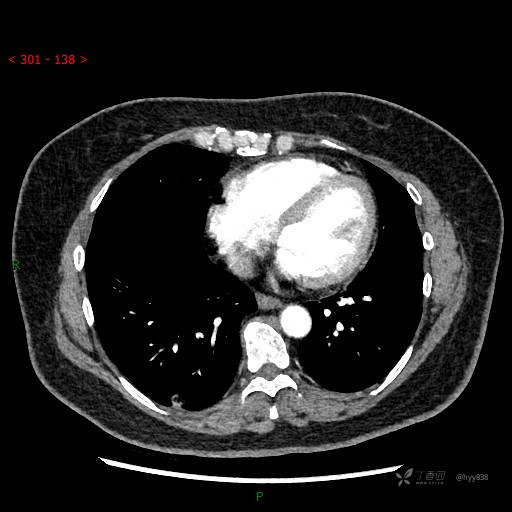

胸部CT增强--动脉期